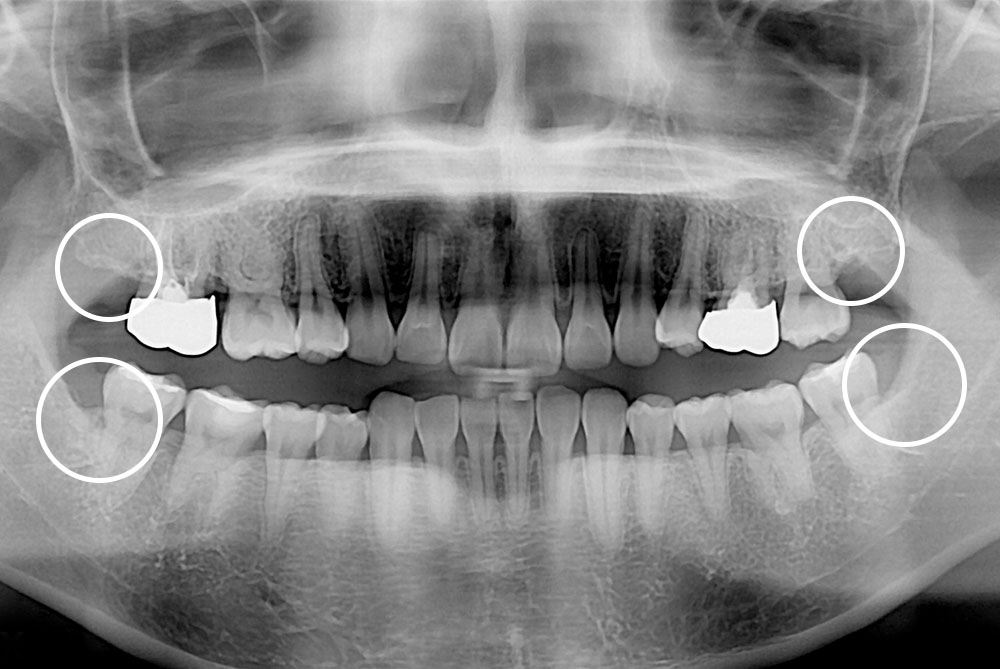

[사랑니] 매복 사랑니 발치

치료후 : 2020-11-18

세종치과는 구강악안면외과학 박사이신 원장님이 발치하는 치과입니다.